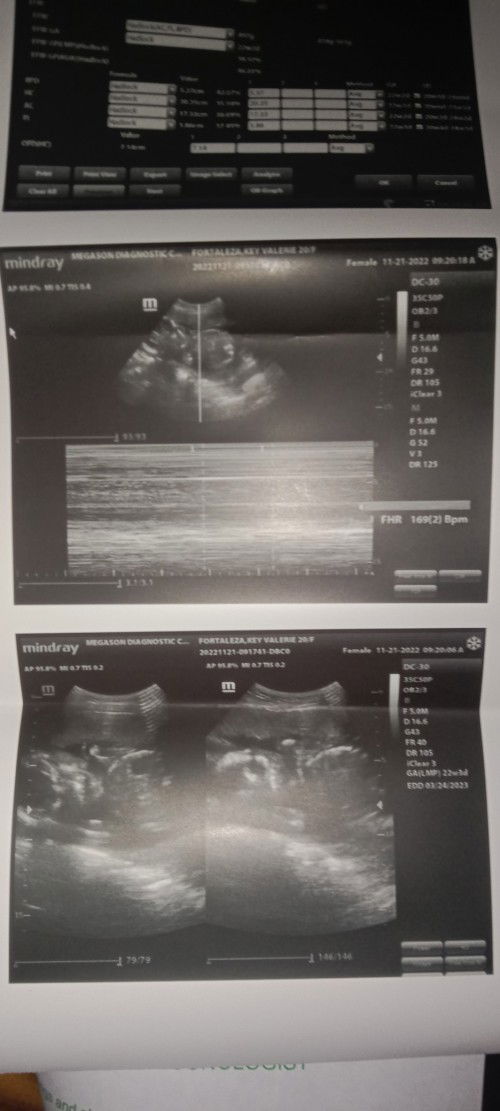

BAKIT PO DI PA MAKITA ANG GENDER NG BABY KO 22WEEKS AND 2 DAYS NAPO.

Good day po nag pa ultrasound po ako tapos sabi po sa akin ng nag uultrasound di pa daw namin masasabi ang gender dahil maaga pa raw po may possibility po ba na ganon? Marami pong salamat sa sasagot.